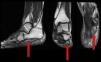

Given the suspicion of noninflammatory involvement, and with the radiograph showing the calcaneal enthesophyte, nuclear magnetic resonance showed substantial atrophy with fat replacement of the abductor muscle of the fifth toe, and several dilated or varicose veins on the inner aspect of the foot along the inferior calcaneal nerve (Fig. 1), compatible with Baxter entrapment neuropathy.